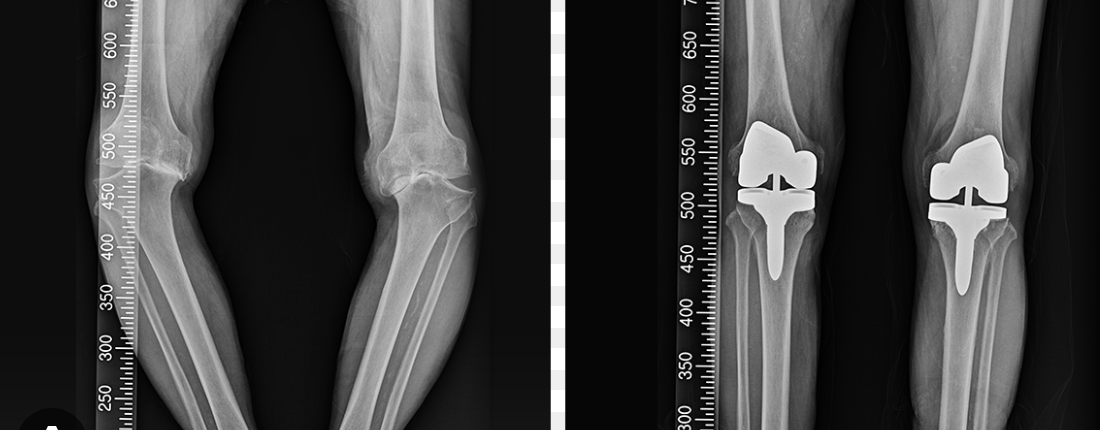

특히 퇴행성관절염의 말기에는 연골이 거의 닳아 없어져 뼈끼리 직접 맞닿으며 극심한 통증을 유발합니다.

인공관절 수술은 이러한 관절 표면을 제거하고 특수 금속과 플라스틱으로 만든 인공 부품을 삽입하는 방식입니다.